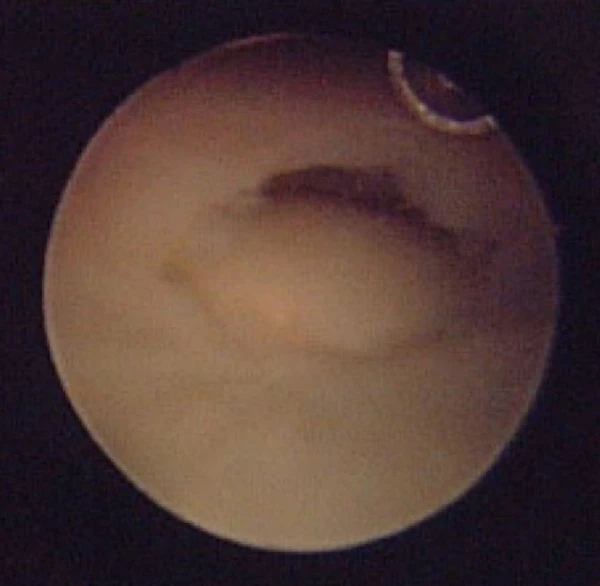

Артроскоп может быть использован во время фиксации для оценки повреждения мягких тканей и конгруэнтности суставной поверхности, что может повысить точность выравнивания суставных поверхностей. К структурам риска относятся треугольный фиброзно-хрящевой комплекс и ладьевидно-полулунная связка. Следует учитывать повреждения ладьевидно-полулунной связки при переломах шиловидного отростка лучевой кости, когда линия перелома выходит дистально в ладьевидно-полулунном промежутке[1].